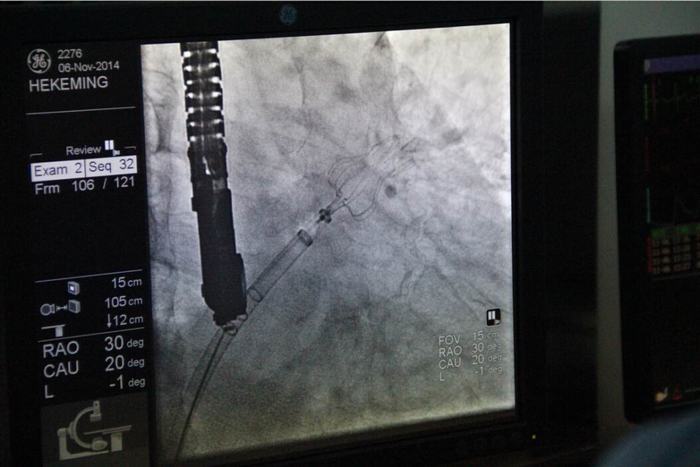

延安大學(xué)咸陽醫(yī)院順利完成西北地區(qū)首例左心耳封堵術(shù)

順利完成西北地區(qū)首例左心耳封堵術(shù)

2014年11月6日在我院董事會(huì)、院領(lǐng)導(dǎo)及心血管病醫(yī)院各級(jí)領(lǐng)導(dǎo)的大力支持下,由德籍華人李教授及兩名美國(guó)專家的協(xié)助,心血管病醫(yī)院張玉順院長(zhǎng)親自手術(shù),在心臟導(dǎo)管室、外科手術(shù)室及B超室醫(yī)護(hù)人員的全力配合下,經(jīng)過一小時(shí)緊張而有序的工作,順利完成了西北地區(qū)首例“左心耳封堵術(shù)”。此手術(shù)創(chuàng)傷小,痛苦少,恢復(fù)快,預(yù)后好。為目前根治房顫導(dǎo)致中風(fēng)最先進(jìn)及可靠的方法,避免了長(zhǎng)期服藥的副作用,減輕了患者的經(jīng)濟(jì)負(fù)擔(dān)。該項(xiàng)技術(shù)國(guó)際領(lǐng)先,國(guó)內(nèi)剛剛引進(jìn)。此手術(shù)的順利開展預(yù)示著我院醫(yī)療診治及介入手術(shù)水平已跨入國(guó)內(nèi)先進(jìn)行列,與國(guó)際接軌,填補(bǔ)了西北地區(qū)空白,為廣大患者帶來福音。

心導(dǎo)管室

曹妙云